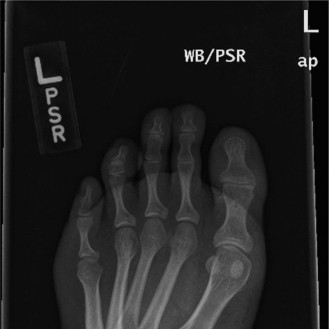

Plain Radiographic Evaluation

Anteroposterior, lateral, and mortise views of the right ankle demonstrated a highly comminuted intra-articular fracture of the distal tibia, extending into the tibial plafond. Significant articular depression and metaphyseal comminution were evident. There was an associated transverse fibular fracture approximately 5 cm proximal to the ankle joint, accompanied by lateral talar subluxation. The overall pattern was consistent with a high-energy axial load injury. The mortise appeared significantly widened, suggesting syndesmotic disruption and loss of the lateral collateral ligamentous restraint.

Computed Tomography and Three Dimensional Mapping

Following initial stabilization and application of a spanning external fixator, a high-resolution Computed Tomography scan of the ankle with fine 1mm axial cuts and multiplanar reconstructions (coronal and sagittal) was obtained. CT imaging is mandatory in the evaluation of pilon fractures to delineate the extent of articular involvement, fragment displacement, and comminution for precise pre-operative planning.

The CT confirmed an OTA/AO 43-C3 pilon fracture with extensive articular depression and displacement of the central die-punch fragments. The articular surface was shattered into the classic three primary fragments described by Topliss et al., the medial malleolus, the anterolateral (Chaput) fragment, and the posterolateral (Volkmann) fragment, alongside severe central impaction. The sagittal reconstructions revealed a 12mm articular step-off and a large central void in the metaphyseal bone where the cancellous bone had been crushed by the impacting talus. The coronal views highlighted the severe varus angulation of the distal tibia and the impaction of the medial shoulder of the talus into the medial plafond.